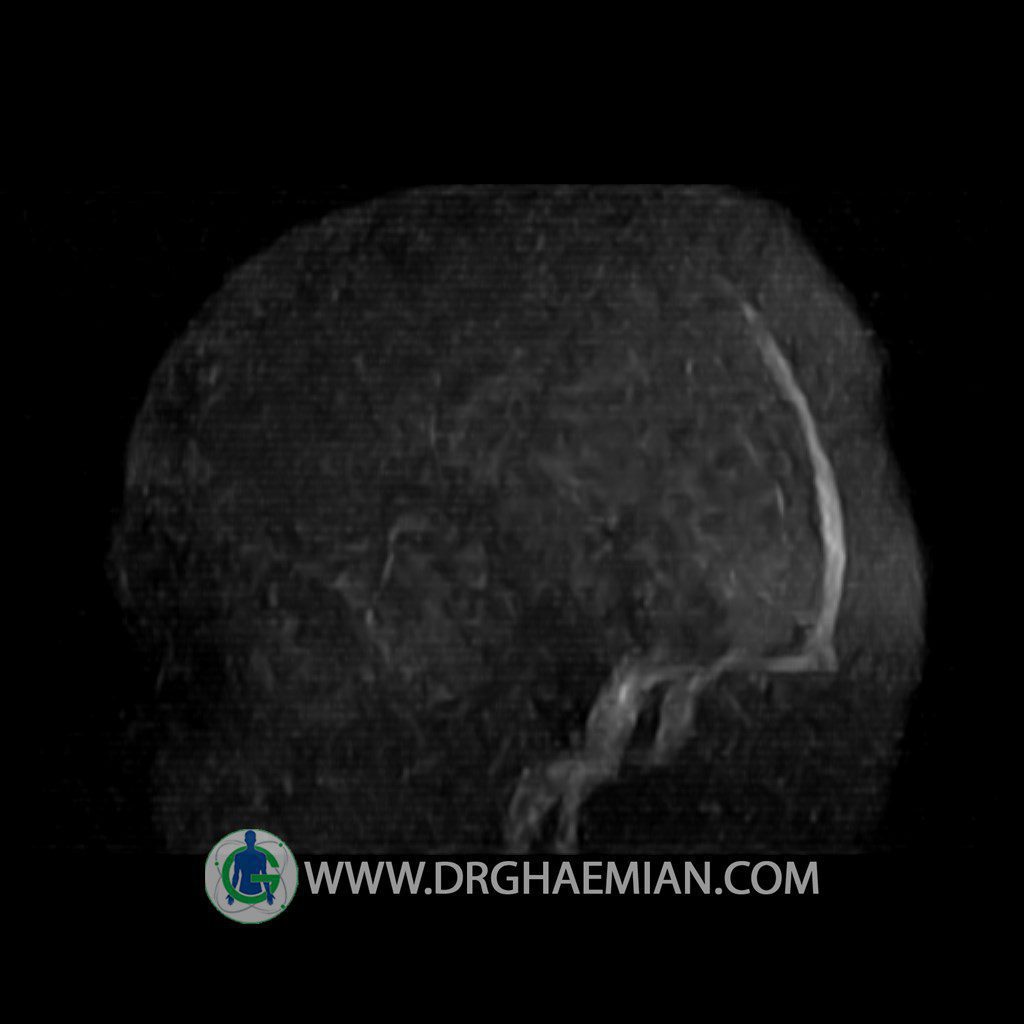

ام آر وی یک روش تصویربرداری دقیق و غیر تهاجمی است که برای معاینه ورید های بدن و ارزیابی سلامت رگ ها استفاده می شود. ورید ها خون را از اعضای بدن به قلب باز می گرداند تا دوباره اکسیژن و مواد مغذی به خون داده شود. ام آر وی جریان خون را ارزیابی و موارد غیرعادی مضر مانند لخته های خونی را شناسایی می کند. در این کیس ترومبوز دیواری مغز در سینوس عرضی راست و ترمبوز جزئی در سینوس عرضی چپ دیده می شود.

Technique: TOF ( time of flight ).

Images of the venous cranial vessels demonstrates a superior sagittal sinus of normal caliber with normal arrangement of draining superficial cerebral veins.

– Narrowing of left transverse sinus with filling defect & inthimal irregularity

suggestive for partial thrombosis

– Inthimal irregularity in anterior wall of right transverse sinus suggestive for mural thrombosis

are seen